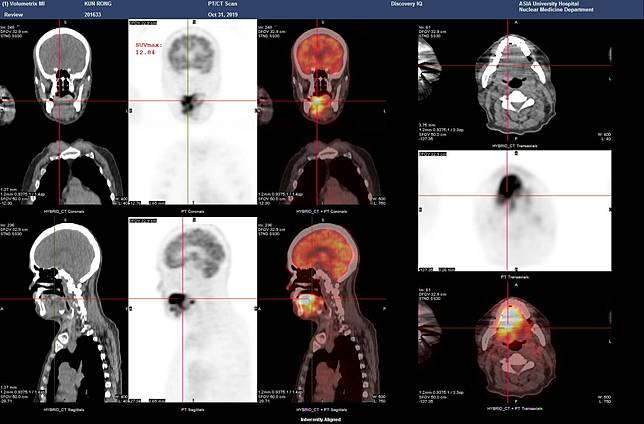

台中60歲李先生因長期香菸、檳榔、酒精不離身,兩年前口腔內發現3公分腫塊,但他置之不理,導致日前就醫時口腔、舌頭都已潰爛,確診為口腔癌第四期,目前透過手術取出全部舌頭及部分下頷骨,並安排化療及放射治療,雖然吞嚥及說話功能仍需長期復健,但李先生仍堅強面對,不放棄任何治癒的希望。

亞洲大學附屬醫院耳鼻喉部主治醫師黃純惟表示,患者到診時嘴巴痛到張不開、整根舌頭腫大潰爛,且因脖子的淋巴結多處轉移,平時根本難以開口說話,最後也只能足不出戶,尤其疼痛越來越劇烈,靠著每天吃止痛藥過日,最後連吃藥都還是痛到睡不著。

黃純惟介紹,手術切除病灶是治療口腔癌最重要的步驟,如李先生已確診為第四期,必須大範圍切除病灶,包括舌頭、部份下頷骨以及頸部淋巴結廓清等,再搭配化學治療和放射治療,才有機會提升存活率,另外因舌頭完整切除,後續也需接受語言及吞嚥治療,恢復說話和進食功能,至於患者術後顏面缺損,可藉由顏面重建手術提升自信。